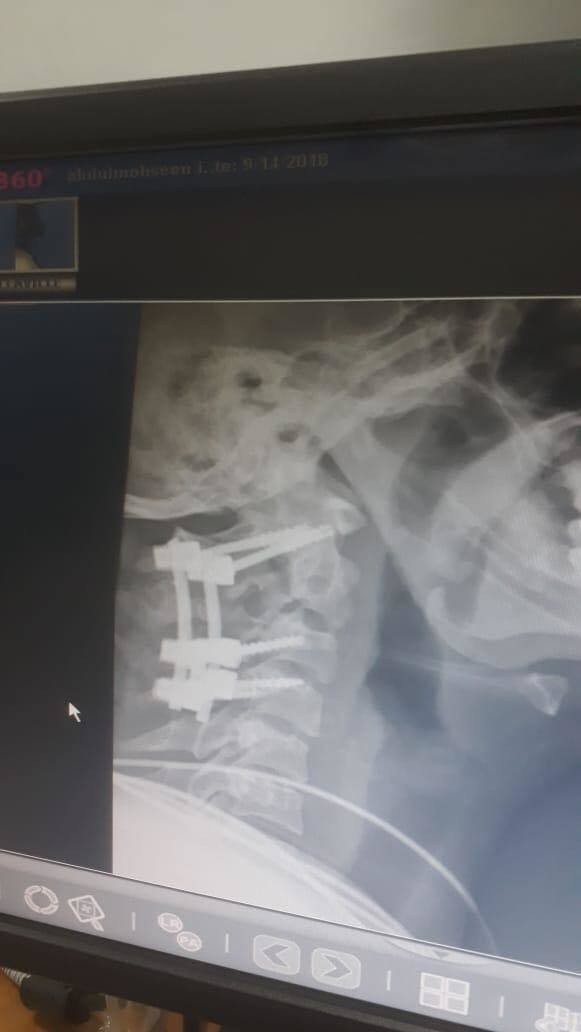

جراحه دقيقه اعلي الفقرات العنقيه

جراحه دقيقه اعلي الفقرات العنقيه بالمستشفي السعودي الالماني بالرياض تنقذ حياة مواطن سعودي.

تمكن فريق جراحة العمود الفقري بالستشفي السعودي الالماني بالرياض المكون من استشاري جراحة العمود الفقري د ابراهيم العسيري ود حازم فريد بفضل الله من إنقاذ حياة مواطن سعودي يبلغ من العمر عشرون عاما وذلك باجراء جراحه في منتهي الدقه والصعوبة وهي عباره عن تثبيت كسر غير مستقر بالفقره العنقيه الثانية اثر حادث مروري حيث تكمن الخطورة في احتمالية إصابة اعلي جزء من الحبل الشوكي لوجود الكسر اعلي الفقرات العنقيه وأسفل الجمجمه مباشرة وقربه الشديد من الحبل الشوكي الذي قد يعرضه للإصابة .وقد تم تثبيت الكسر بواسطة مسامير واعمده وعمل التحام للفقرات العنقيه العليا والمتعارف عليه عالميا بانه افضل الطرق الجراحيه لمثل هذا النوع من الإصابات وتمت العملية بنجاح تام وغادر المريض المستشفي مترجلا معافا بفضل الله بعد يومين فقط من الجراحه... وبفضل كفاءة الكادر الطبي في المستشفى.